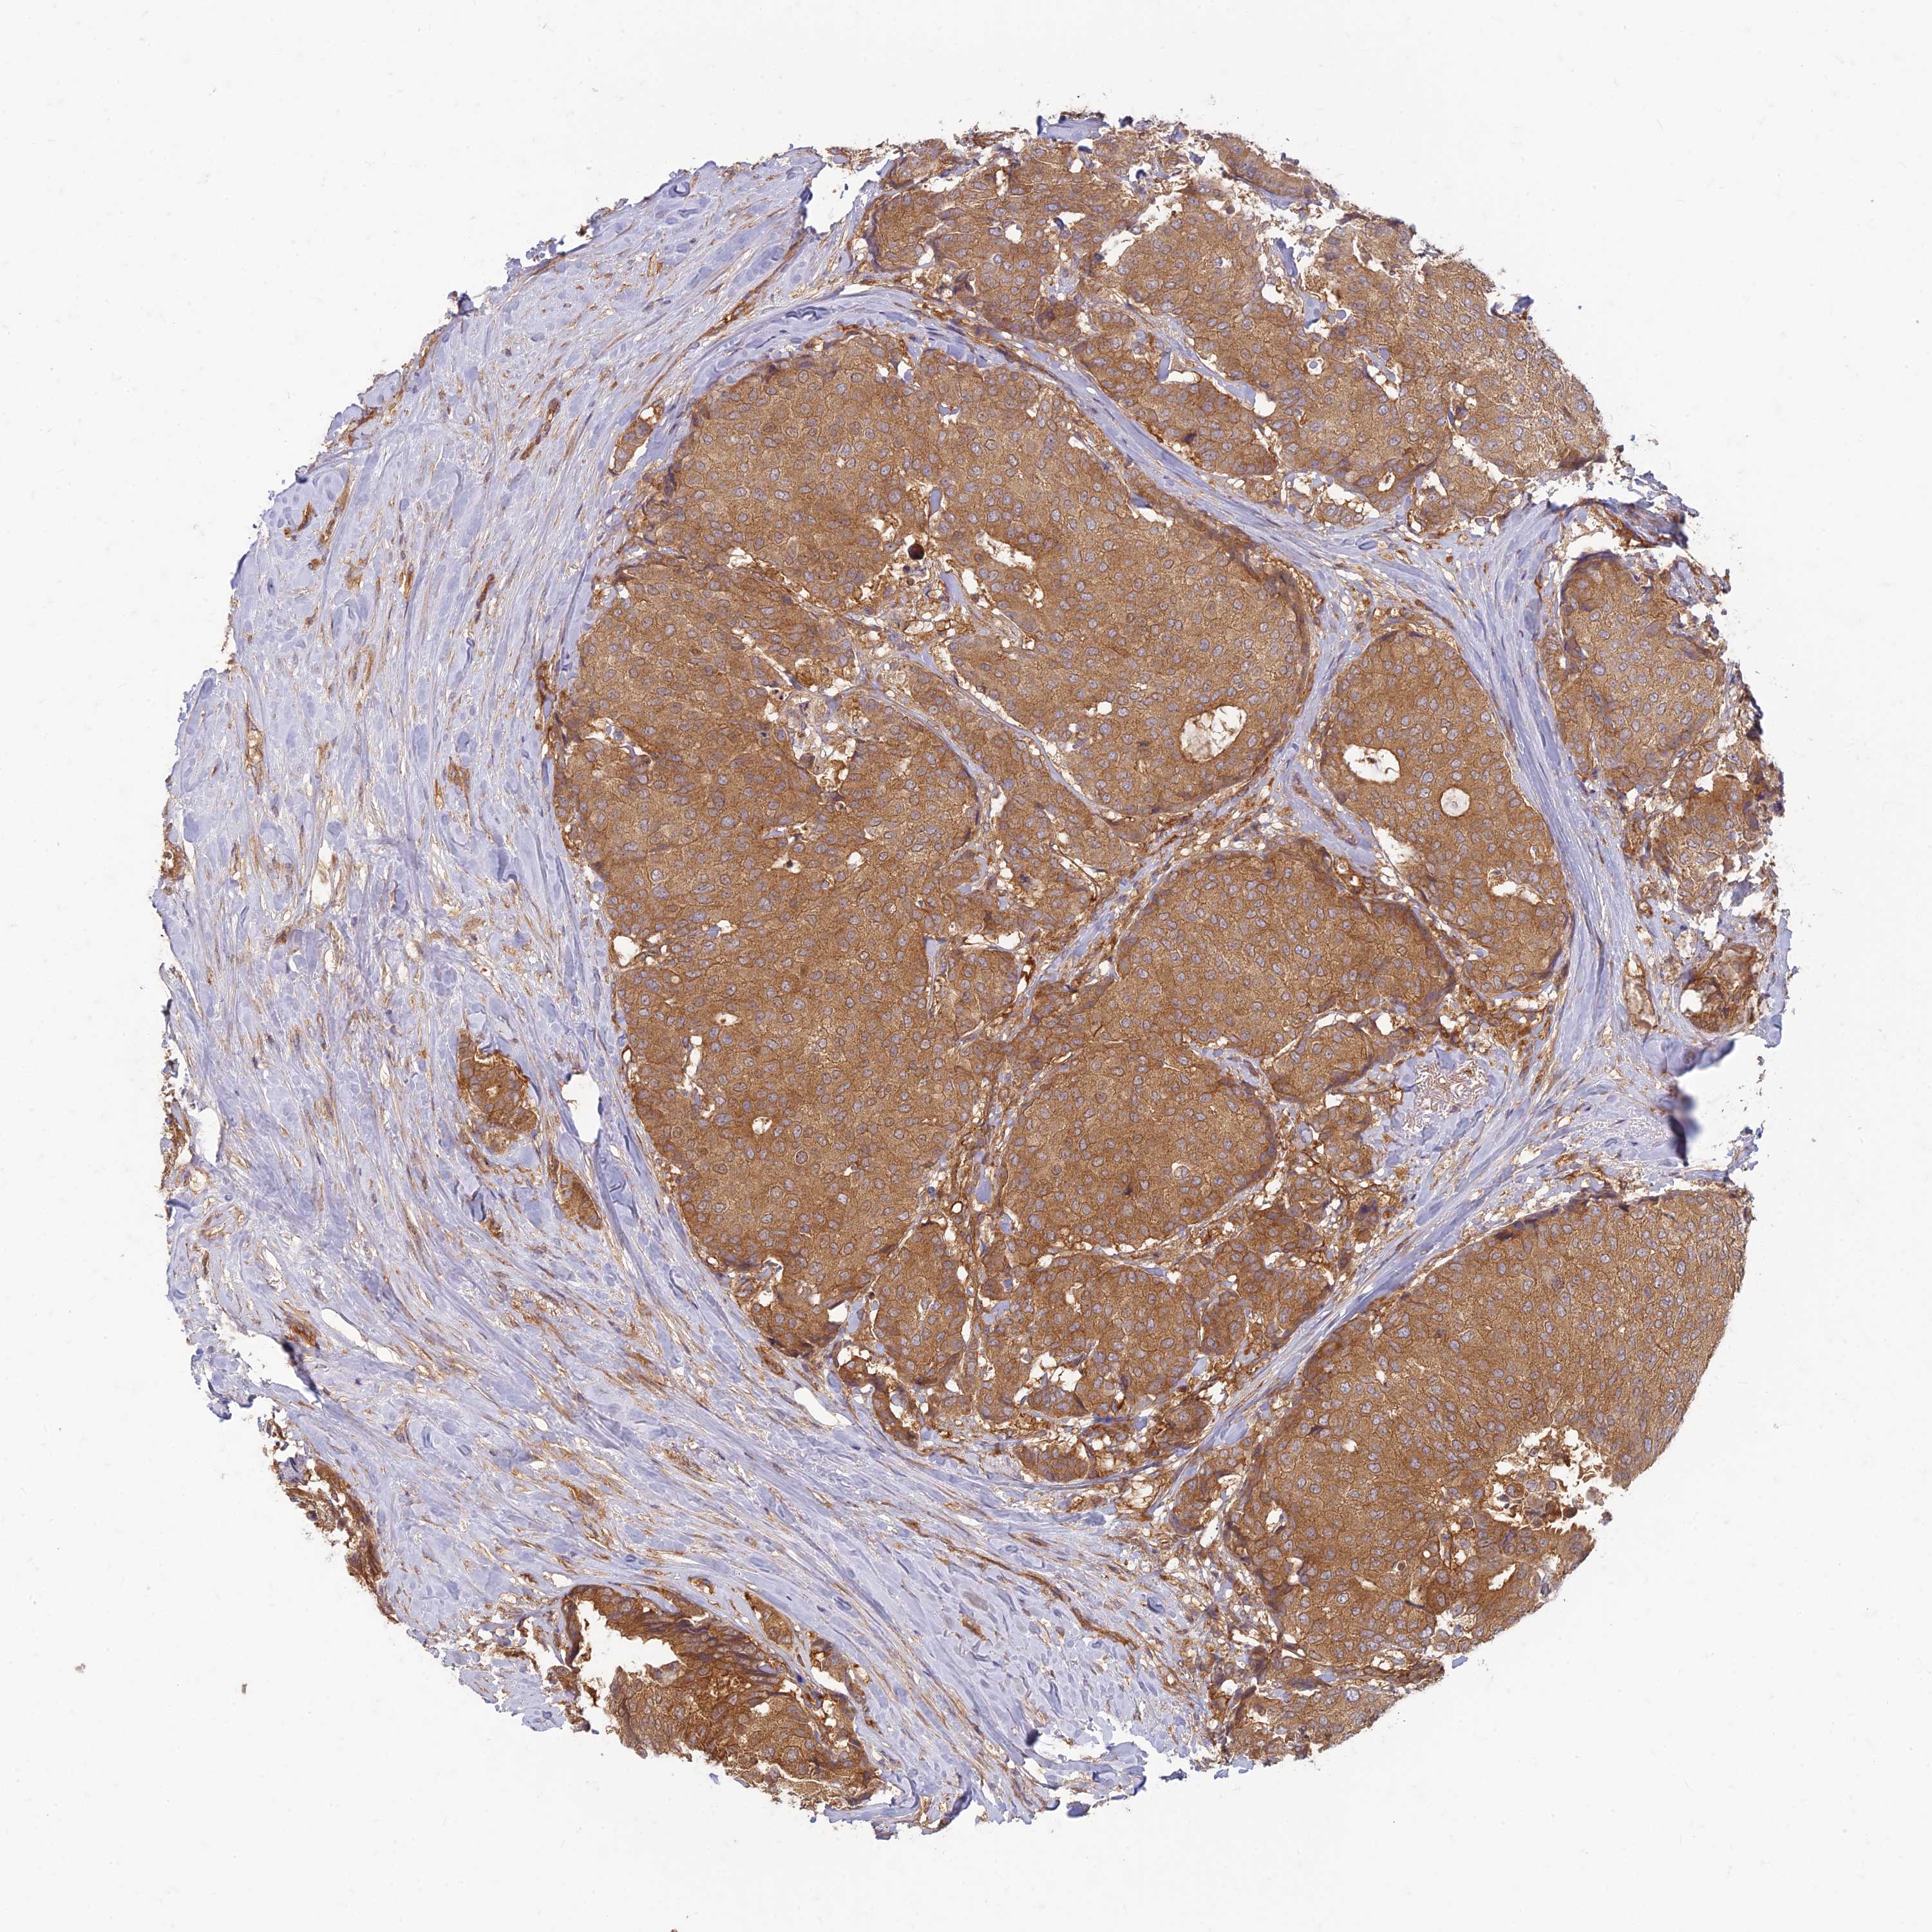

CANCER BREAST CANCER Show tissue menu

BRCA TCGA BRCA VALIDATION PROTEIN EXPRESSION

Breast cancer

Human cancer

Breast invasive carcinoma